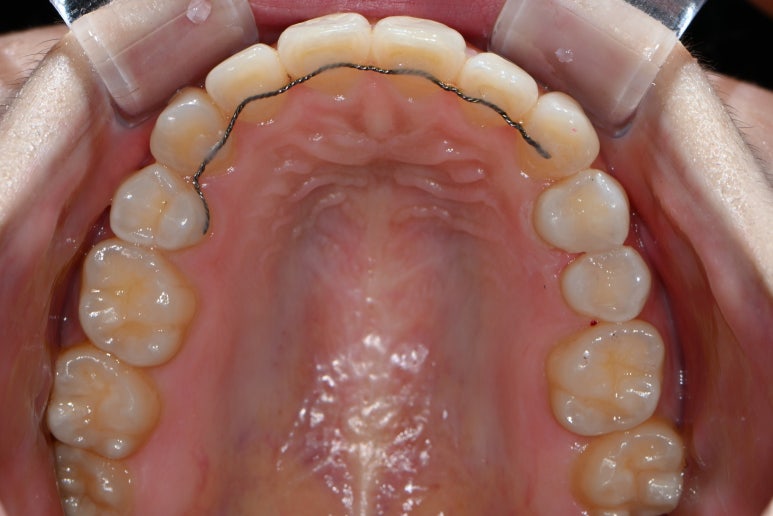

이젠 감쪽같이 치료가 마무리 되었습니다.

잘 보시면 똑같은 부위에 멍들어 보이던 치아가 이젠 깨끗이 치료된 것을 보실 수 있을거에요!

기억자와 니은자처럼 생긴 레진 인레이 두개가 예쁘게 자리잡아 있네요. 사랑니를 보기 위해 찍었던 파노라마 사진에서 확인할 수 있었답니다. 완전 깔끔 !!!